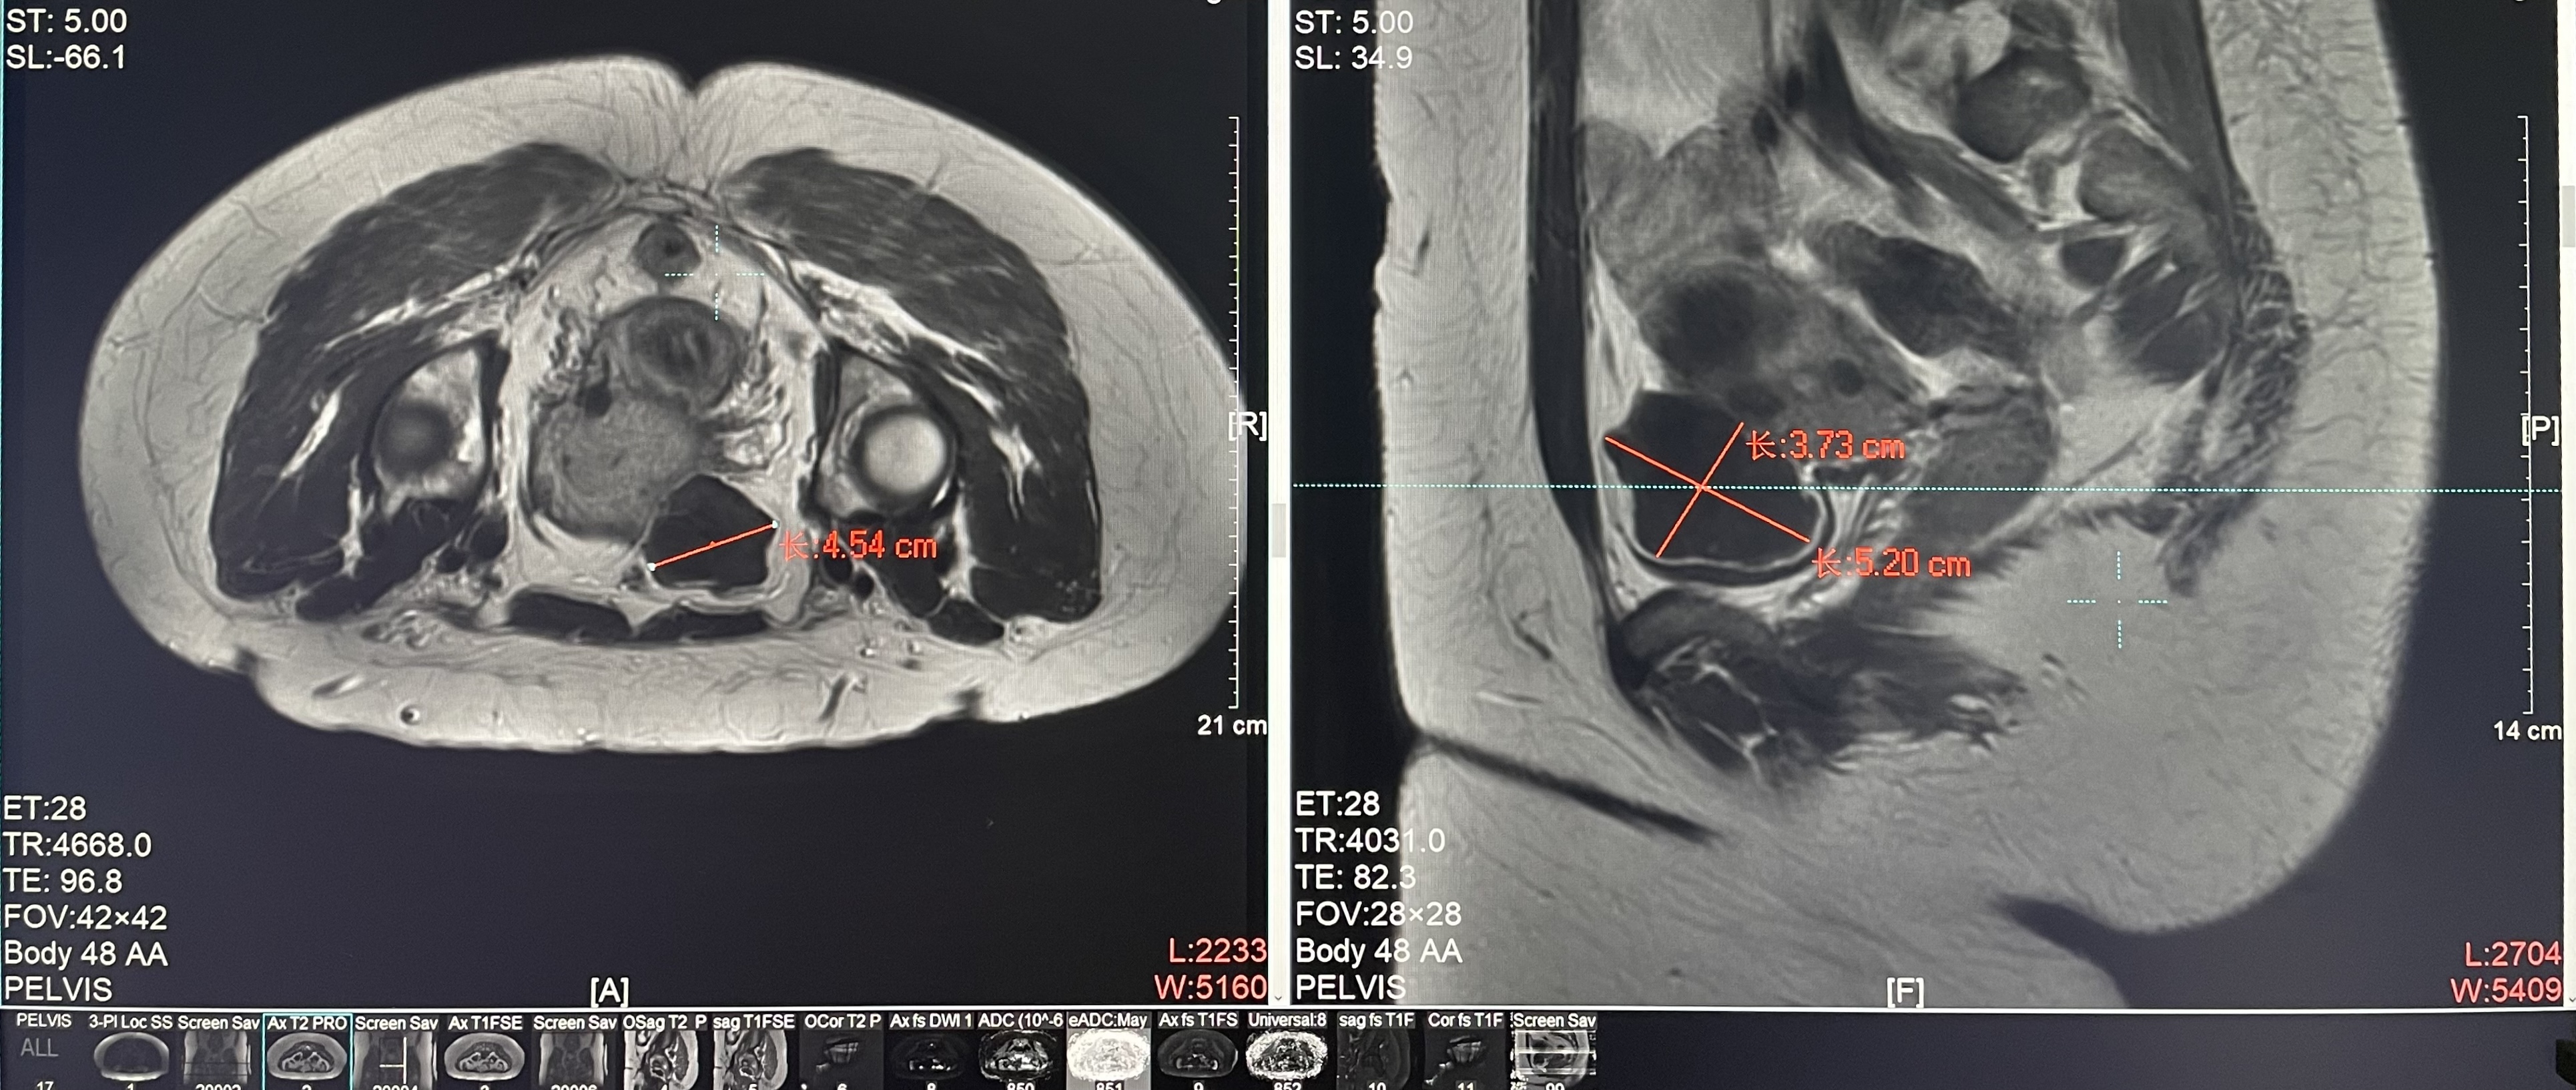

Uterine fibroids

Patient Information:Female,38

Diagnosis: Uterine fibroids

Tumor size: about 38*40*42mm

ROT depth: The ROT center of the tumor is mm from the skin

Postoperative evaluation: Postoperative enhanced imaging showed a good overlap between the ablation area (right) and the tumor area (left), the non-perfusion area was continuous and consistent.

Conclusion:It has a excellent ablation effect on this tumor, and the temperature rise curve during treatment is in line with expectations. The 240CEM area of each treated target is large, full and continuous.The ablation effect was very good,the NPV volume ratio was about 87.88%.